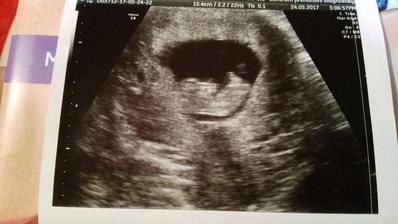

24.5. 2017 kontrolní ultrazvuk. Jsi krásný medvídek a srdíčko tluče překrásně